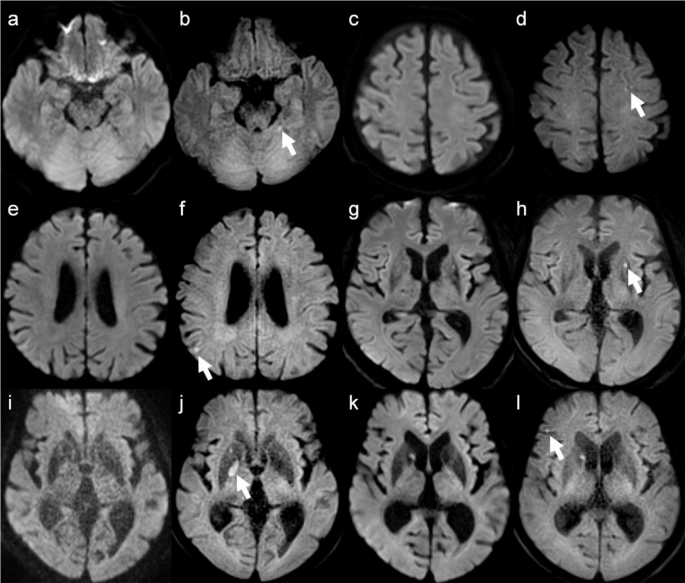

Six of the 10 acute or subacute infarct lesions were in the cerebellar hemisphere near the cerebellar tentorium, frontal cortex, parietal cortex, putamen, and globus pallidus (Fig. 1). All these lesions were very small and located in regions prone to artifacts or near areas of hemosiderin deposition. Additionally, two cases were asymptomatic, while the duration after symptom onset in the remaining four cases ranged from 1 to 4 days, indicating that most lesions were shortly after the onset of infarction.

Representative images in patients with acute or subacute infarction. The white arrows indicate infarctions in the cerebellar hemisphere near the cerebellar tentorium (a, b), left frontal cortex (c, d), right parietal lobe (e, f), left putamen (g, h), right globus pallidus (i, j), and right frontal cortex (k, l). SS-EPI DWI (a, c, e, g, i and k); TGSE-BLADE DWI (b, d, f, h, j and l). The lesions are detectable only on TGSE-BLADE DWI but are unclear on SS-EPI DWI due to proximity to cortex, cerebellar tentorium, or hemosiderin deposition in the basal ganglia.